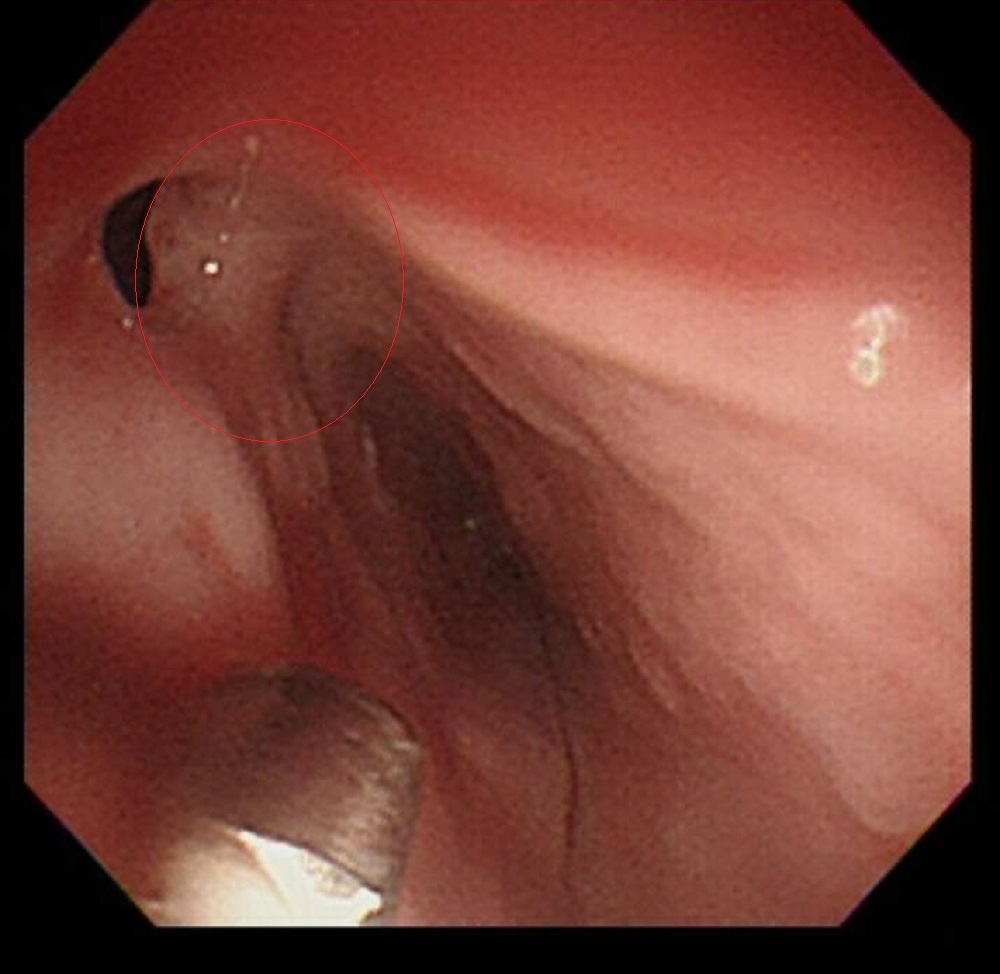

▲內視鏡下的食道腫瘤(紅圈處)。(彰化醫院提供)

王棋新指出,蔡先生的食道癌是位於喉嚨下方的鱗狀上皮細胞癌,約2公分大,是最不好處理的位置,在亞洲地區的食道癌以此類居多,主要是因為吸菸、飲酒、檳榔,以及飲食品質不佳引起。蔡先生有30多年抽菸及喝酒習慣,是食道癌高危險族群,研判是引發食道癌的重要因素。